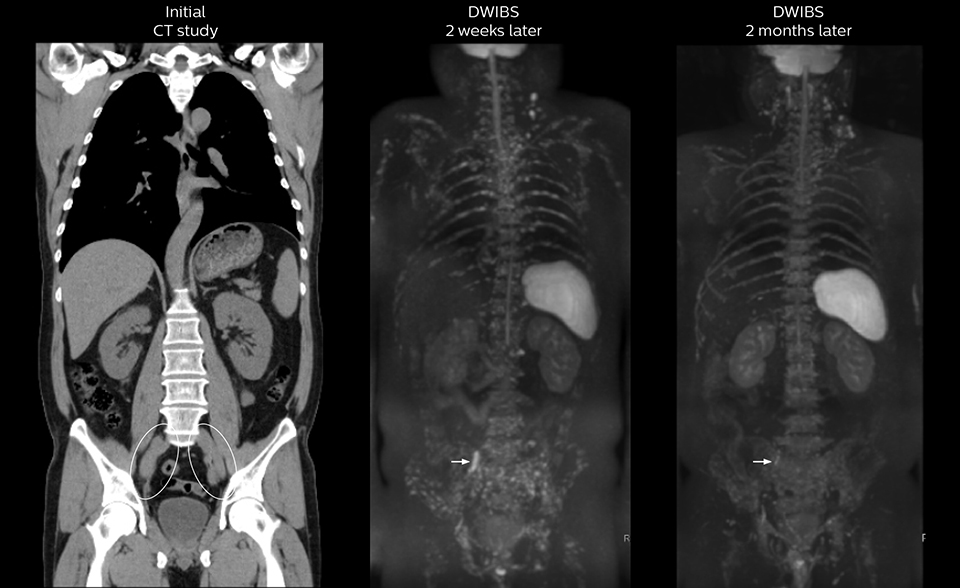

As oncologists and surgeons have learned more about DWIBS, referrals for the exams have increased. In 2015, the 326-bed hospital’s radiology department doubled their number of whole body DWIBS exams compared to 2014.

Mr. Naka remembers some cases where DWIBS provided remarkable information. “In one example, DWIBS visualized bone lesions that could not be seen on PET or SPECT. In another case we had found a bone lesion when a normal L-spine scan for narrowing of the disk space was done. One extra DWIBS scan (2 stations, 8 minutes) demonstrated a lesion that later was confirmed to be the primary region of cancer.”

In certain cases, radiologists now choose DWIBS to make diagnoses that used to depend on nuclear medicine studies. “We don’t have SPECT or PET in our hospital, so for instance for visualizing metastasis and monitoring the effect of treatments such as chemotherapy or radiotherapy, we used to refer patients outside the hospital. Now, these patients are sent to MRI for our whole body protocol with DWIBS,” Mr. Naka says.